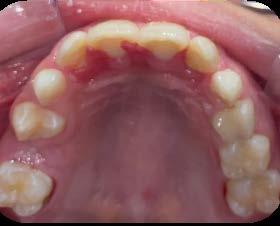

Entre los elementos que conforman al sistema estomatognático, están los dientes caninos, órganos dentales esenciales en la fisiología masticatoria; punto de unión y continuidad estética entre la línea de la sonrisa y el corredor posterior del arco dental, además de que ejercen la función de pilares estabilizadores en la oclusión fisiológica (Figura 1).

Los caninos son indispensables durante los movimientos de lateralidad y vitales para la continuidad de los arcos dentales, tanto en la dentición decidua como en la permanente; son responsables del funcionamiento y la armonía oclusal. Su posición adecuada en el arco asegura un buen contorno de la cara, sonrisa agradable y armónica con la estética facial. (Figura 2).